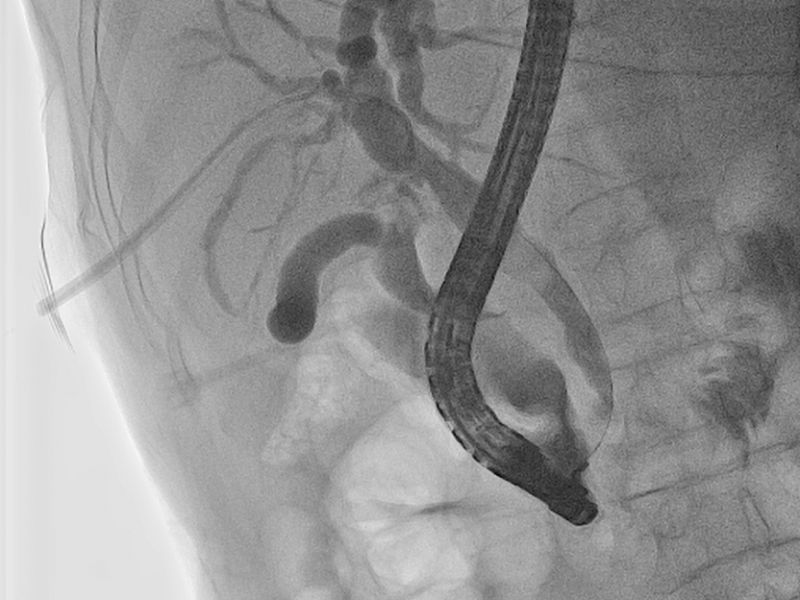

1月14日,在介入科、麻醉科多学科协助下,介入科丁文金副主任医师经PTCD管植入导丝及鞘管至十二指肠乳头开口处,消化内二科向仍运医师在十二指肠镜直视下插入导丝至PTCD鞘管成功会师,从而进入胆总管,切开十二指肠乳头,网篮取净胆总管结石,手术成功,拔除PTCD管。术后常规抗炎及支持治疗,患者康复顺利,于1月23日痊愈出院。

取净胆总管结石